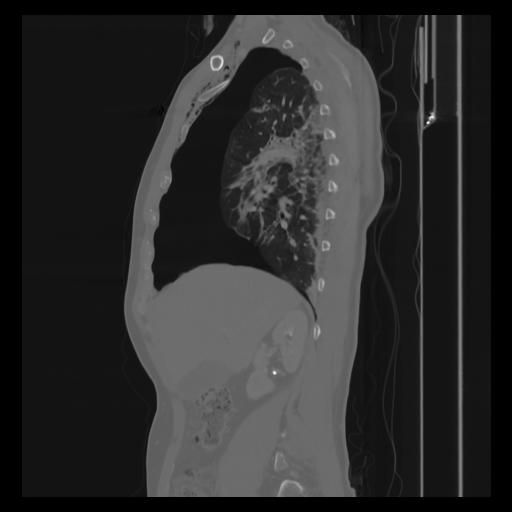

30 CUERPO,CE,Sagittal,3.000,CUERPO,Sagittal,